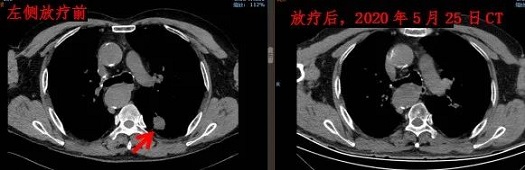

治疗完后,老李很快恢复了正常的生活和工作。下面是老李放疗前和2020年5月的CT对比。

幸运的是老李虽然双肺转移,但都是单发病灶,且病灶不大。肿瘤放疗科给患者制定了立体定向放射治疗计划,每侧病灶大剂量放疗8次。既控制了肿瘤,又给患者节省了时间和费用。

50多岁的老李2016年发现右肺癌,2016年5月老李做了右肺上叶切除术+淋巴结清扫术,术后病理提示右上肺中分化腺癌。2017年8月发现双肺转移,随后给予化疗和靶向治疗,无效。2018年3月来肿瘤放疗科放疗。